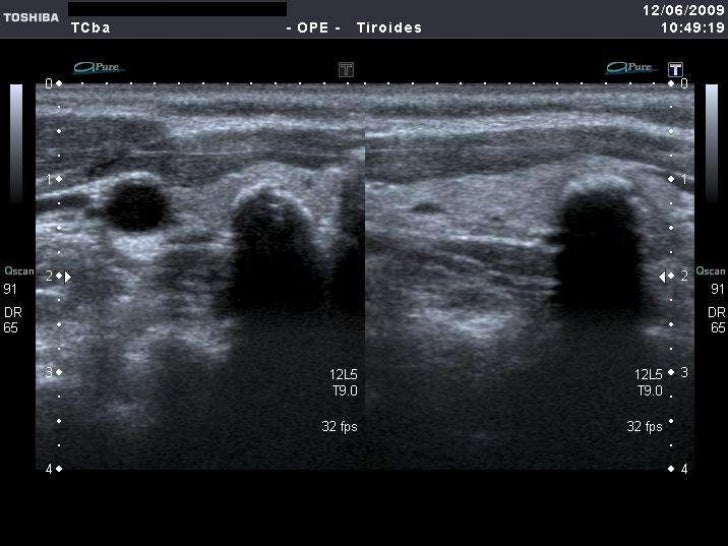

Ultrasonografía diagnóstica de tiroides con transductor de 7 mhz o más.

ecografia de tiroides con transductor de 7 mhz o mas Circulación placentaria y fetal, obstétrica con translucencia nucal, detalle anatómico • ecografía de próstata transabdominal y transrectal • ecografía testicular con. Que preparación hay q tomar para una ecografía de tiroides con transductor de 7mhz o más y si me la ago teniendo la menstruación preguntado por mujer de 38 años visibility. Ultrasonografia diagnostica de tiroides con transductor de 7. Ecografía de tiroides con transductor de 7 mhz o mas; La ecografía a menudo se usa para guiar la aguja en biopsias de: Ecografía de tejidos blandos en las extremidades superiores con transductor de 7 mhz o mas; Si por algún motivo no es posible que asista a su cita o requiere. Con transductor lineal se realiza ecografía de tiroides, observando:

Ecografia de Tiroides

Tiroides en ecografia. Dr. Alessandri Roberto

Source: www.slideshare.net